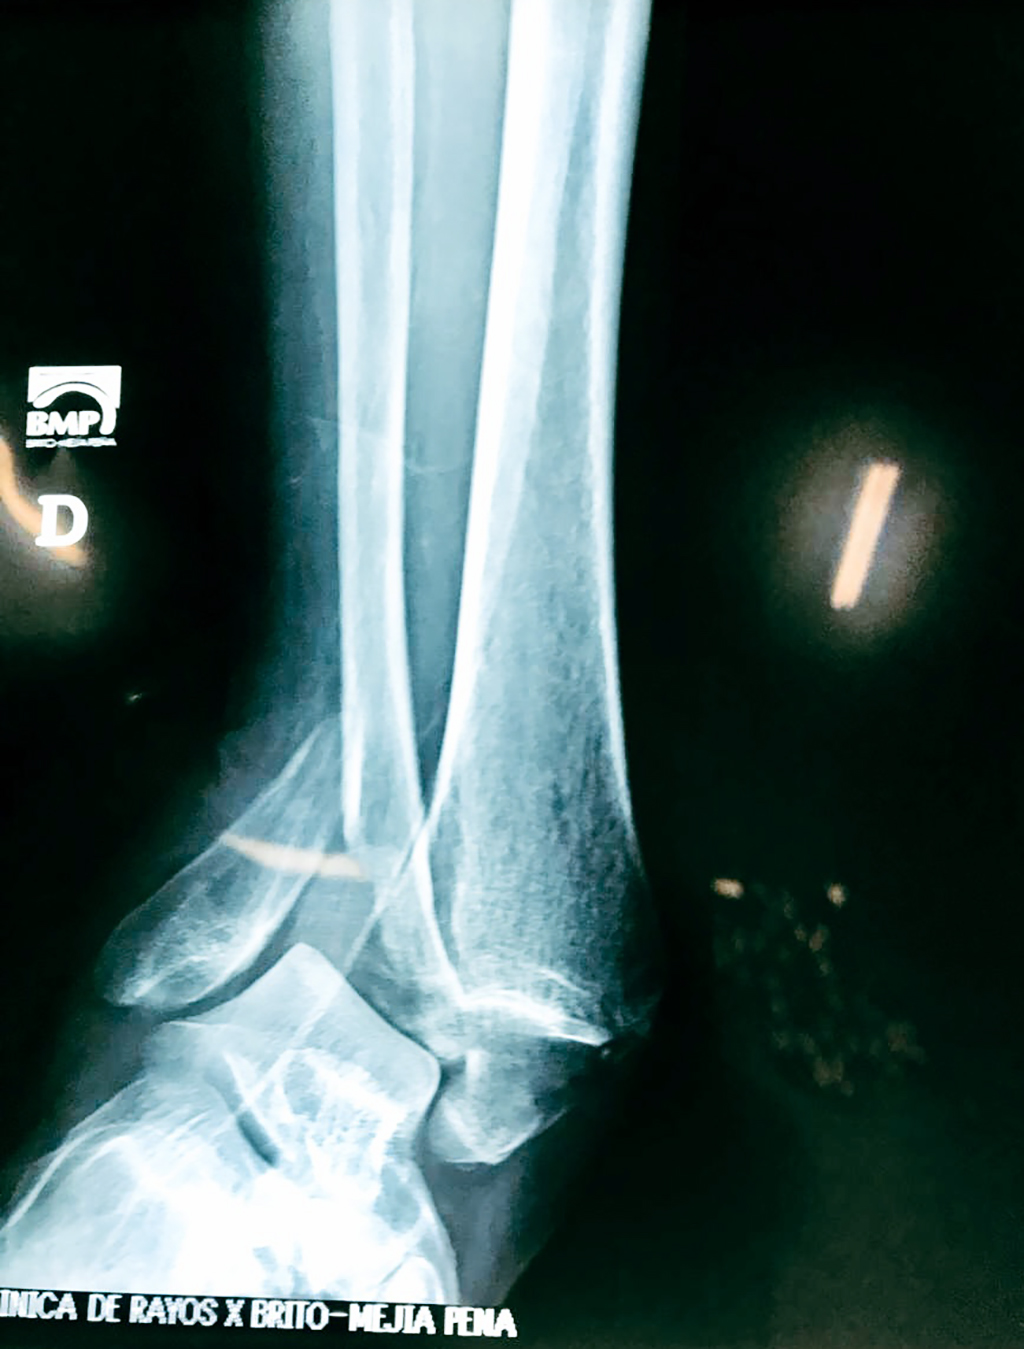

Una fractura de tobillo es la rotura de uno o más de los huesos del tobillo. Estas fracturas pueden ser:

- Completas (el hueso está perforado y está en 2 partes).

- Los extremos de los huesos están desalineados entre sí (desplazados).

Cuando se necesita cirugía, es probable que esta implique el uso de clavijas de metal, tornillos o placas para sostener los huesos en su lugar mientras la fractura se consolida. Los elementos de soporte pueden ser temporales o permanentes.